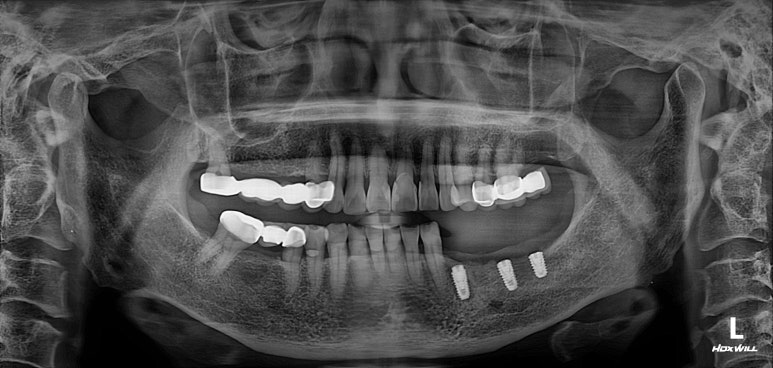

저희 병원에 작년에 오셨던 여자환자분입니다.

왼쪽 아래 어금니가 2개가 없으신 것을 아실 수 있으실텐데,

그 자리에 편측 틀니를 쓰고 계셨고, 너무너무 불편하여 임플란트로 치료 받으러 내원하셨습니다.

왼쪽 아래 큰어금니 두개가 없었고,

교합면 사진을 보시면, 앞의 두 치아에 surveyed crown (서베이드 크라운)을 설치하고 부분 틀니를 사용하게 하심을 단번에 알 수 있었습니다.

중요한 것은 해당 부위의 대구치 두 개를 뽑은지가 너무 오래되셨고, 틀니를 사용하셔서

대부분의 부착치은 (각화치은)이 사라져 있는 상태였습니다.

그래서 유리치은 이식술을 강하게 권유드렸고, 환자분이 다행히도 필요성을 이해해주셨어요.

약 6주 후 왼쪽 아래 어금니 부위에 뼈이식을 동반하여

임플란트 1차 수술을 시행하였습니다.

왼쪽 아래 네 개의 어금니를 만들어 드려야 했기에, 과반수가 넘는 3개의 임플란트 수술을 계획하였습니다.

#34,36,37 자리에 임플란트를 식립할 예정이었어요.

마무리는 갈끔한 엑스레이 사진으로 !!!